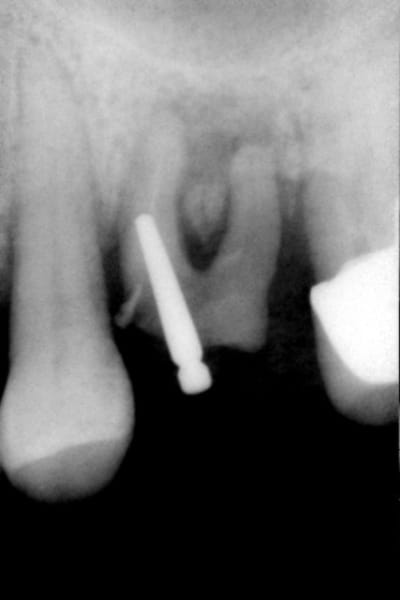

fracture plancher de 16